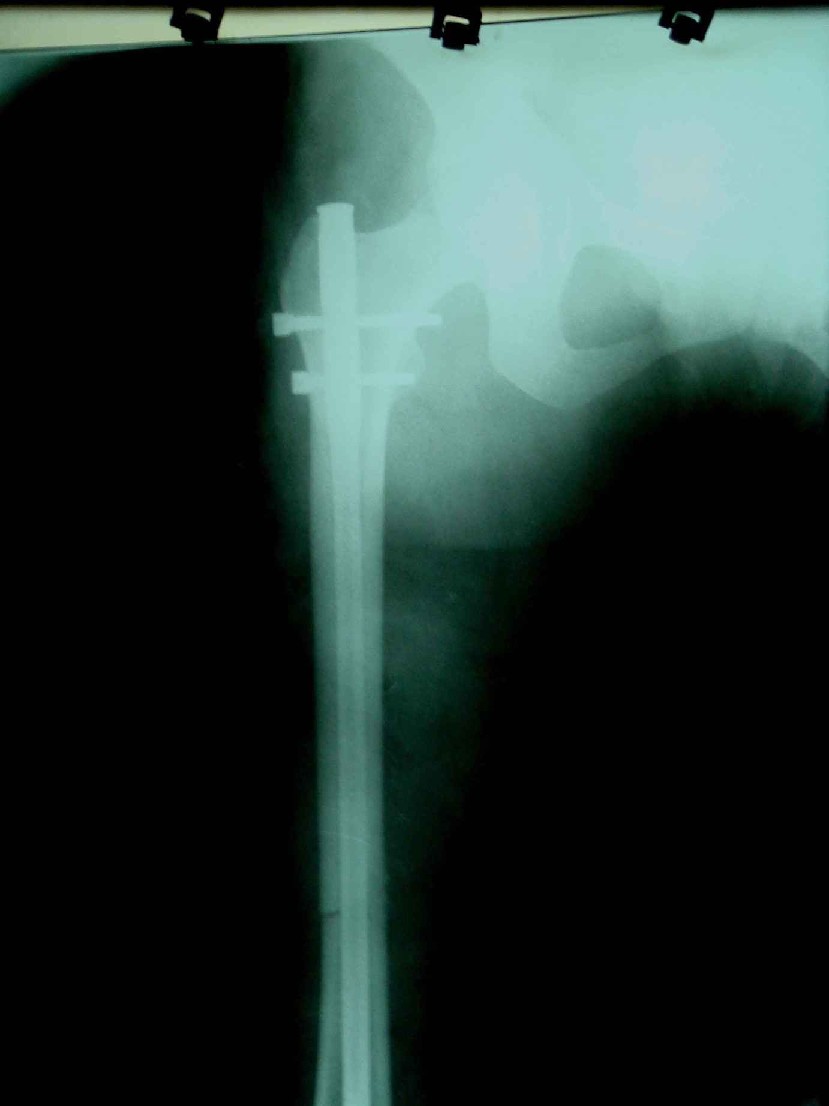

患者,女,因外伤就诊。摄骨盆及右股骨。当时报告骨盆未见明显异常,右股骨中段粉碎性骨折。五天后行股骨中段骨折内固定手术,术中摄床边片示股骨颈骨折。现把术前和术中图像上传。请大家高诊,分析股骨颈骨折是术前漏诊还是其他原因。术前骨盆片右股骨颈显示欠佳是由于股骨中段骨折无法将股骨颈完全显示。

术前片示右股骨颈未见明显骨折征象。如果事先有骨折,由于投照位置原因,骨折线也是完全有可能被挡住重叠而看不见的(并且本例骨折对位良好,更有可能看不到)。所以要凭此判断述前是否有骨折不容易

从上传的照片来看,术前无法诊断骨折。可能是投照角度的问题。

由于术前下段骨折 股骨颈显示不完全所致 很正常啊

当然可能由于术前骨折对位对线良好,有可能观察不到骨折线,有的裂纹骨折平片当时是看不见骨折线的,7天左右才可能由于骨折线水肿&活动等原因从而显示出骨折线;还有投照位置的原因。术前未看见骨折线也属正常现象。

考虑术前骨折(由于投照位置原因,骨折线有可能被挡住重叠而看不见的或骨折处未有移位可能看不到)。术后由于外力作用骨折线增宽而清楚显示)。

术前由于位置原因使股骨颈未全部显示,骨折线与股骨头重叠,骨折也可以使股骨颈缩短

术前所照的片子体位好象有点不标准,右侧股骨颈显示不是很好,没有完全展开,所以不好说术前就一定没有骨折的情况.

楼主给我们大家提供了非常好的片子,感谢!该片股骨颈的骨折术前看不到骨折。这个和体位也有关,但是我们都知道,那些标准的体位是给健康人设计的,外伤比较重的往往都无法标准投照。不知道同行们有没有这样一种感受:发现明显的问题了,就心里比较踏实了,舒坦了,就不容易对其它细节仔细观察了。如果没有发现明显的问题,就仔细的翻来覆去的看。所以这个片子给我们很大的教训:仔细阅片!即便是已经发现问题了。如果非要给鸡蛋里面挑骨头,我认为楼主忽略了右髋关节囊的肿胀,诊断报告应该提一下。外伤的病人我最怕股骨颈的漏诊,一般我都要看软组织。我是一个小医院的,我深有感触,发现骨折不是功劳,而漏诊却是事故,还遭受别人耻笑:放射科的连骨头断没断都看不出来!